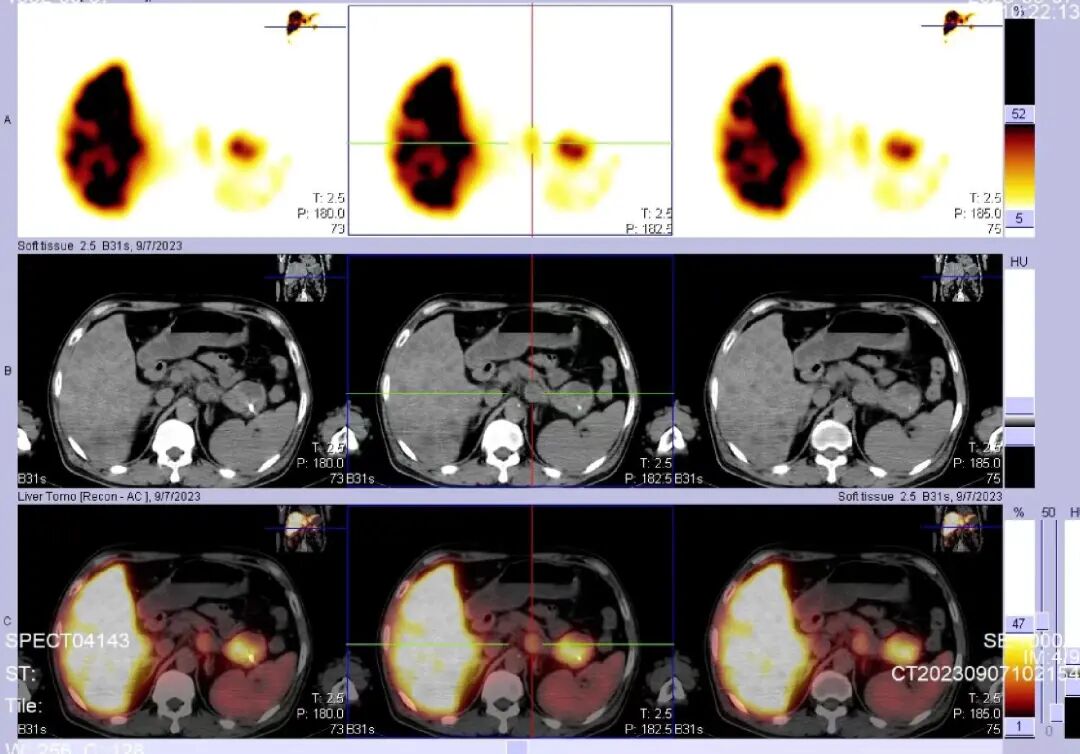

一名61岁男性患有胰腺神经内分泌肿瘤,治疗前已确诊有骨转移、肝脏转移。部分治疗后的影像显示,核素精准“直达”病灶,且有大量放射性药物摄取,这可能预示疗效良好。同时,正常骨骼和脏器对放射性药物没有摄取或摄取极少,因此副作用很小。